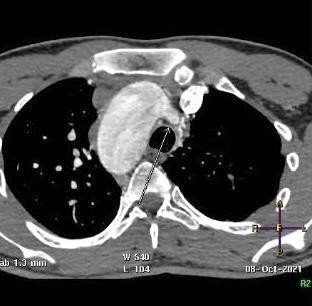

CT angiogram of chest shows complex cardiac disease including right-sided aortic arch (Figure 1), ventricular septal defect and overriding aorta (Figure 2). Non-visualization of the pulmonary trunk (Figure 3).

Small blind-ended artery arising from the aortic arch at the take-off point of the left brachiocephalic artery (Figure 5) with non-visualization of left main pulmonary artery (Figure 3A). Multiple small arterial collaterals at the left hilum supplying the relatively hypo-plastic left lung (Figure 3A).

Figure 3: Contrast-enhanced CT chest axial (A), sagittal and coronal (B) views, showing an arterial supply to the right upper lobe arising from the descending aorta. Also there is an absent left pulmonary artery with multiple small collaterals at the left hilar region. Relative hypo-plastic left lung.